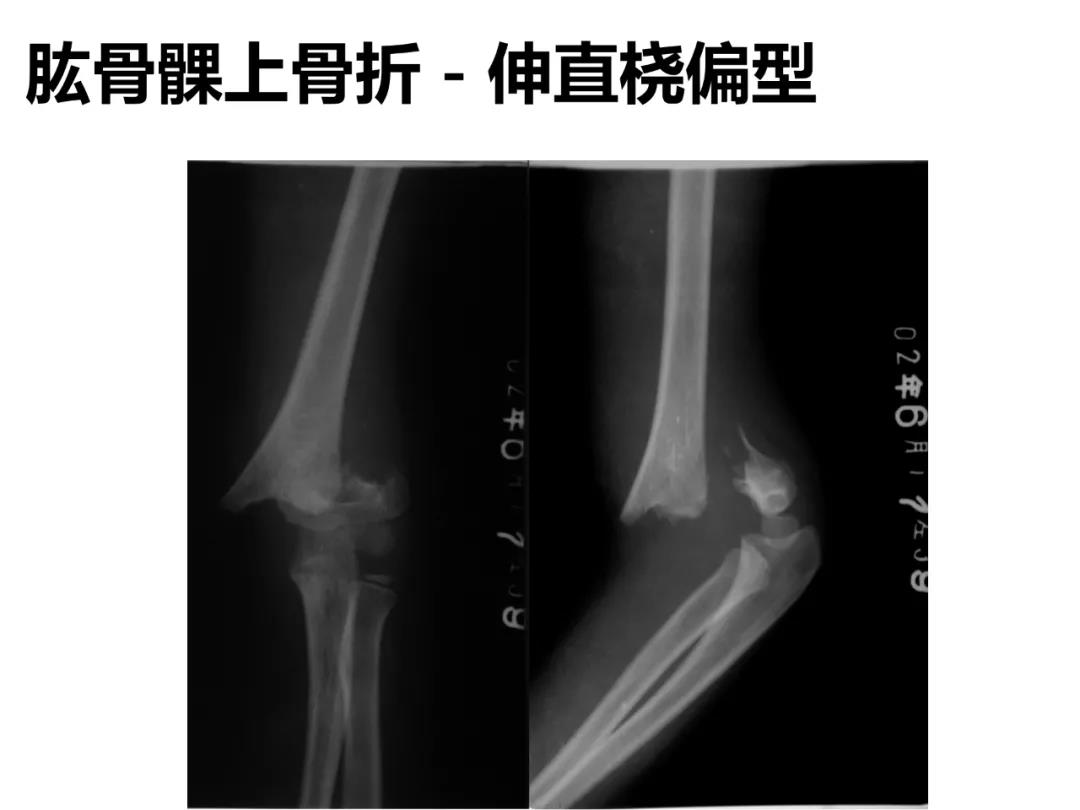

小儿骨科X线片汇总,临床读片宝典!